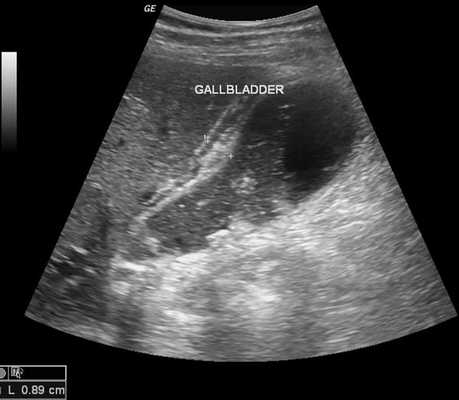

2. УЗИ при остром бескаменном холецистите:

• УЗИ (черно-белое изображение):

о УЗ-картина острого бескаменного холецистита аналогична УЗ-симптоматике острого калькулезного холецистита, за исключением отсутствия вколоченного конкремента

о Утолщение стенки желчного пузыря (>4 мм):

- Гипоэхогенная, слоистая/исчерченная структура

о Растяжение желчного пузыря:

- Обычно заполнен сладжем

- Гидропс; размеры заполненного анэхогенной желчью желчного пузыря: продольный >8 см, поперечный >5 см